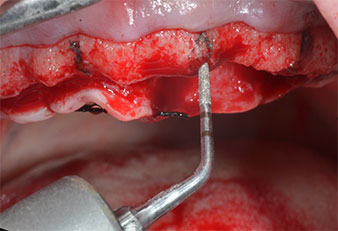

A flame-shaped, diamond-coated piezoelectric instrument (Piezomed I1) was used to mark the implant positions and to perform pilot preparation (Fig. 3). Care was taken to use an up and down movement, with reduced power, full irrigation and low pressure (below 300 g). Next a pilot instrument (Piezomed I2A/I2P) was applied for the initial 2 mm diameter enlargement of the implant sites (Fig. 4), followed by a 3 mm insert (Fig. 5).